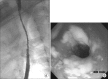

Esophageal candidiasis is commonly seen in immunocompromised patients; however, candida esophagitis induced stricture is a very rare complication. We report the first case of esophageal stricture secondary to candidiasis in a glycogen storage disease (GSD) 1b child. The patient was diagnosed with GSD type 1b by liver biopsy. No mutation was found in the G6PC gene, but SLC37A4 gene sequencing revealed a compound heterozygous mutation (p.R28H and p.W107X, which was a novel mutation). The patient's absolute neutrophil count was continuously under 1,000/µL when he was over 6 years of age. He was admitted frequently for recurrent fever and infection, and frequently received intravenous antibiotics, antifungal agents. He complained of persistent dysphagia beginning at age 7 years. Esophageal stricture and multiple whitish patches were observed by endoscopy and endoscopic biopsy revealed numerous fungal hyphae consistent with candida esophagitis. He received esophageal balloon dilatation four times, and his symptoms improved.